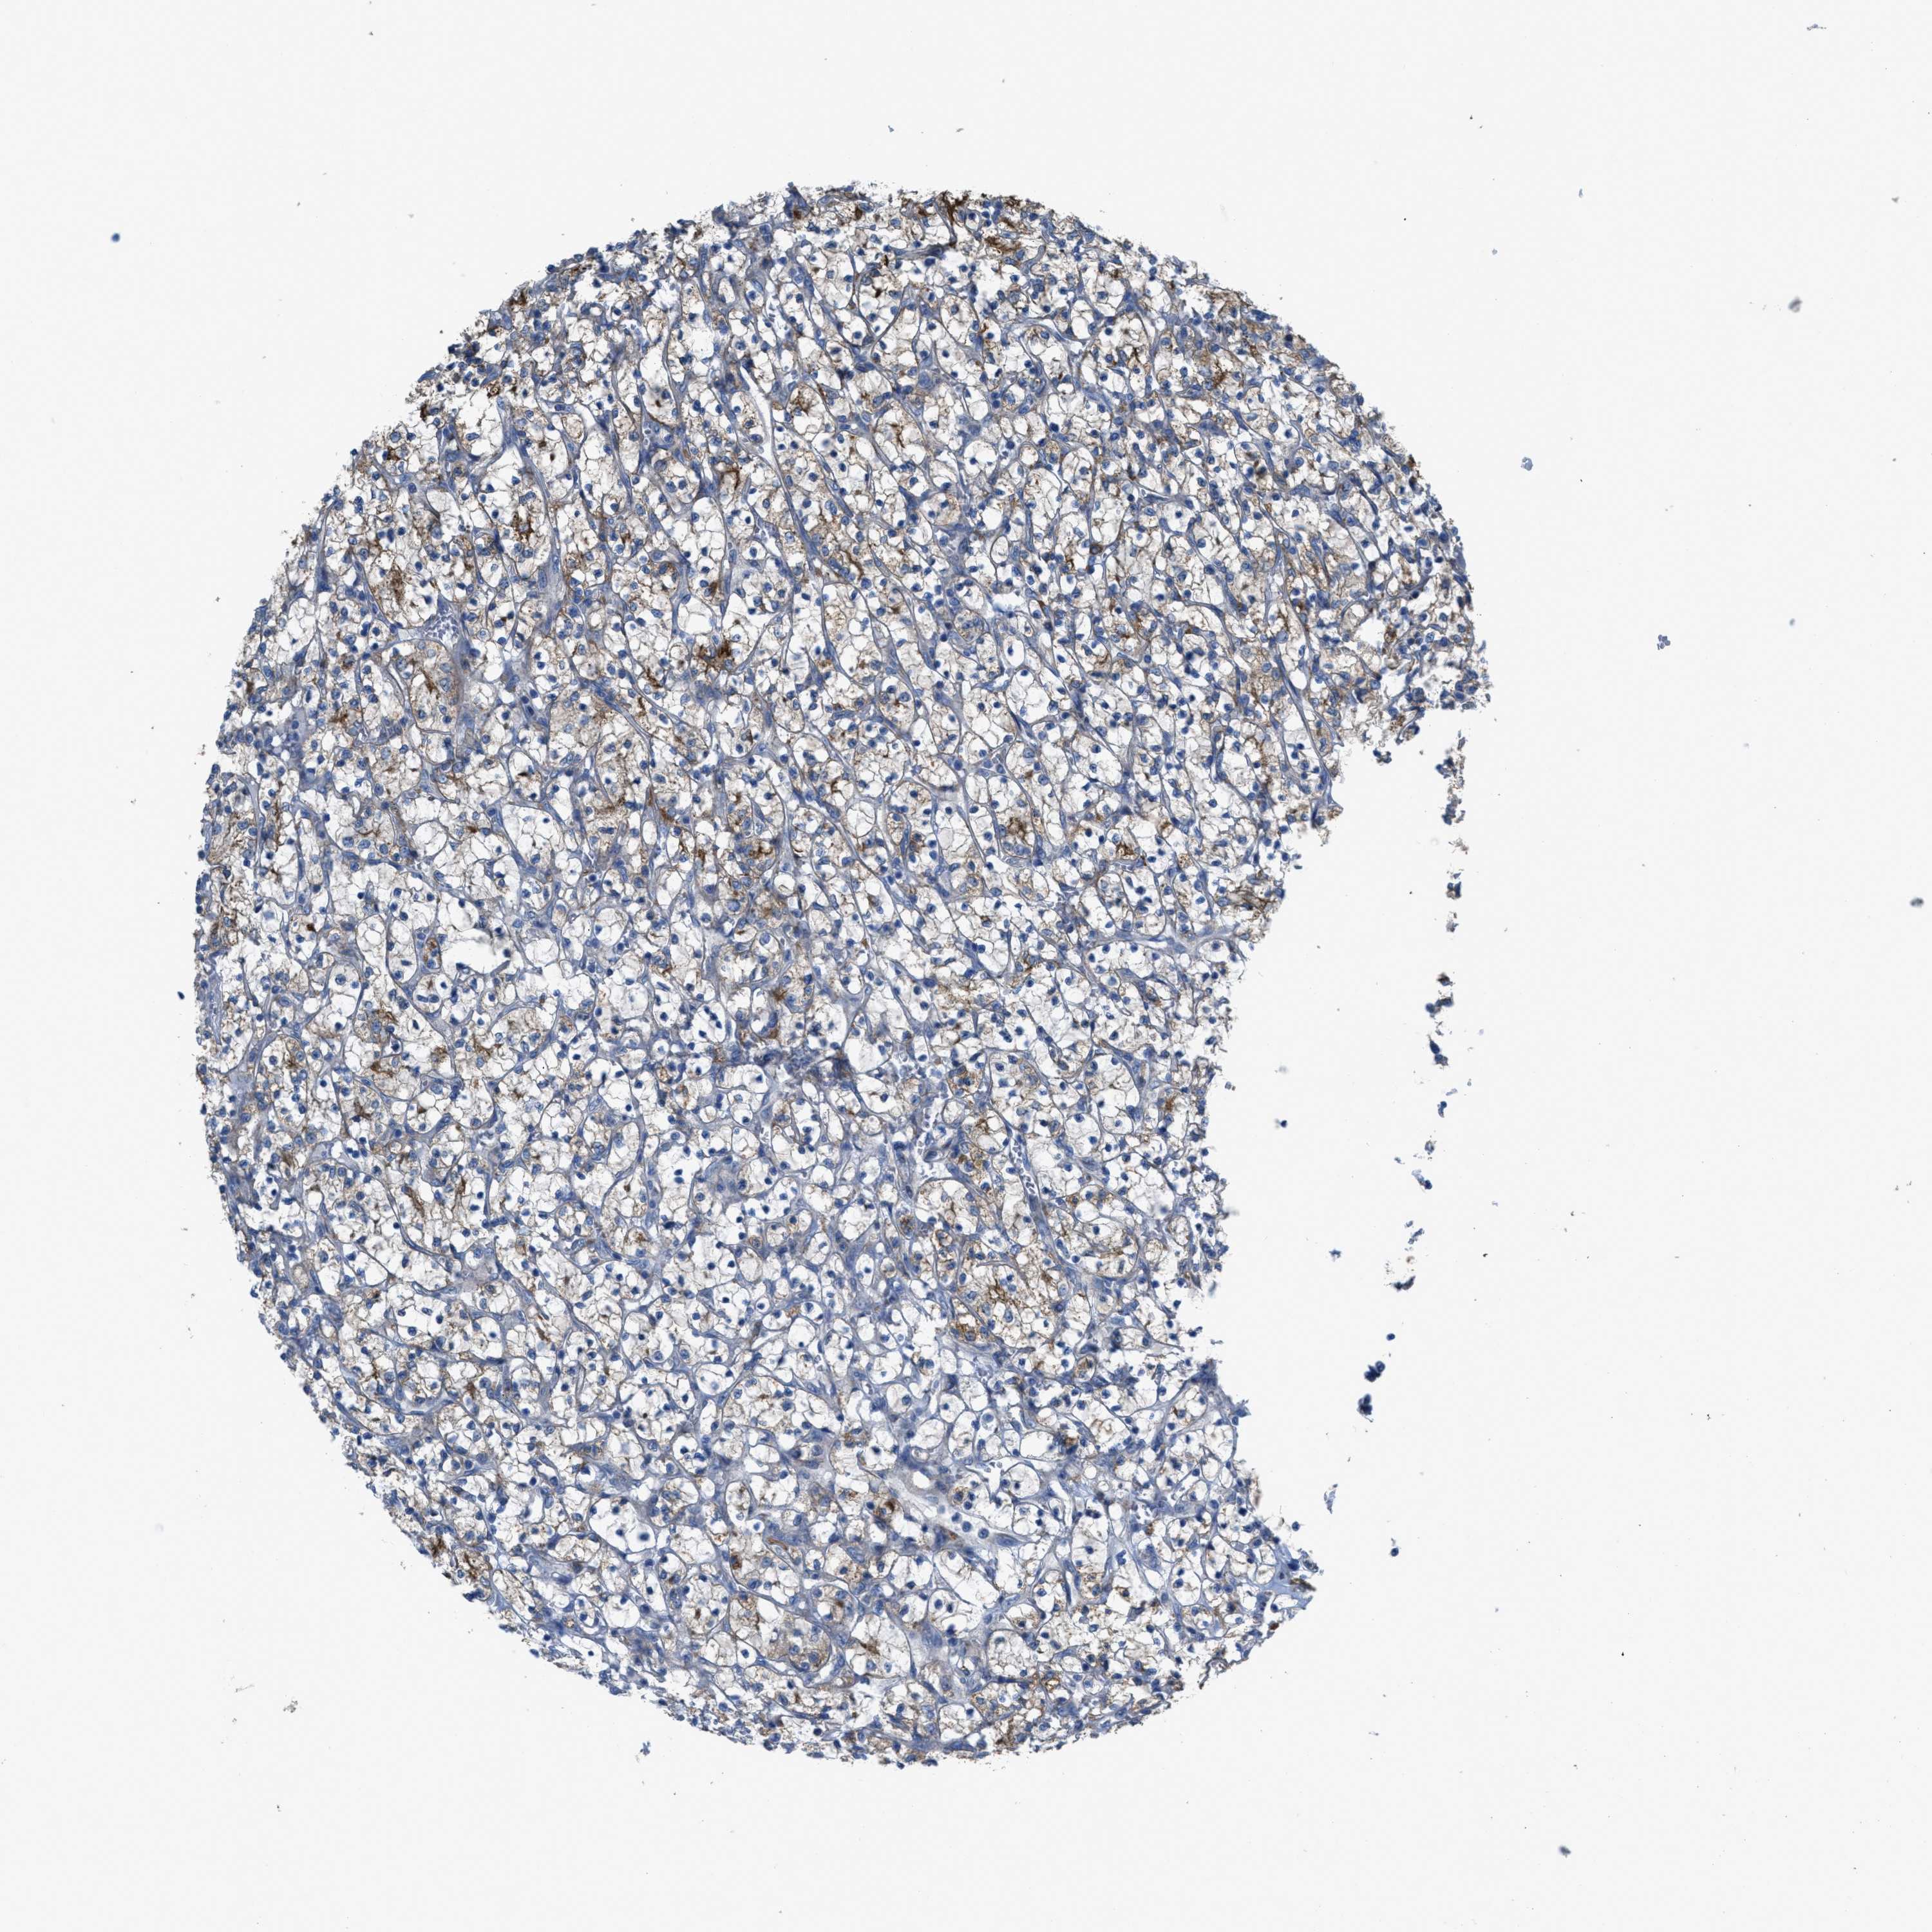

KIDNEY RENAL CLEAR CELL CARCINOMA (TCGA) - Interactive survival scatter ploti

The Survival Scatter plot shows the clinical status (i.e. dead or alive) for all individuals in the patient cohort, based on the same data that underlies the corresponding Kaplan-Meier plots. Patients that are alive at last time for follow-up are shown in blue and patients who have died during the study are shown in red.

The x-axis shows the expression levels (FPKM) of the investigated gene in the tumor tissue at the time of diagnosis. The y-axis shows the follow-up time after diagnosis (years). Both axes are complimented with kernel density curves demonstrating the data density over the axes. The top density plot shows the expression levels (FPKM) distribution among dead (red) and alive patients (blue). The right density plot shows the data density of the survived years of dead patients with high and low expression levels respectively, stratified using the cutoff indicated by the vertical dashed line through the Survival Scatter plot. This cutoff is automatically defined based on the FPKM cutoff that minimizes the p-score. The cutoff can be changed by dragging the vertical line or by entering a cutoff value in the square labeled "Current cut-off".

Under the Survival Scatter plot the p-score landscape (black curve; left axis) is shown together with dead median separation (red curve; right axis). Dead median separation is the difference in median mRNA expression between patients who have died with high and low expression, respectively. It is calculated as follows: median FPKM expression of dead patients with high expression - median FPKM expression of dead patients with low expression. This is intended to aid the user in visually exploring custom cutoffs and the associated p-scores and dead median separation.

Individual patient data is displayed and can be filtered by clicking on one or more of the category buttons on the top of the page. Categories describing expression level and patient information include: high, low, alive, dead, female, male and tumor stages. The scale of the x-axis can be toggled between linear and log-scale by clicking on the "x log" button. Mouse-over function shows TCGA ID, patient information and mRNA expression (FPKM) for each patient.

& Survival analysisi

Kaplan-Meier plots summarize results from analysis of correlation between mRNA expression level and patient survival. Patients were divided based on level of expression into one of the two groups "low" (under cut off) or "high" (over cut off). X-axis shows time for survival (years) and y-axis shows the probability of survival, where 1.0 corresponds to 100 percent.

EGFR is potential prognostic, high expression is favorable in Kidney Renal Clear Cell Carcinoma (TCGA)

: 29.68

Average pTPM 52.9

Number of samples 521